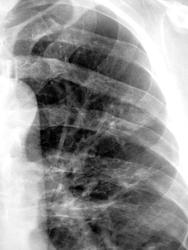

Инфицированные МБТ заполненные ретенционные бронхиальные кисты легких. Не исключаю, что фтизиатры обозначили эти изменения как множественные туберкулёмы. Имеется положительная динамика. С уважением Nikolas

В областной конторе не мудрствуя лукаво выставили инфильтративный (возможно, практически это верно). А, Вам часто приходилось видеть такое инфицирование ретенционных кист МБТ. У меня, это второй случай, за всю лучевую практику.

Лечили в ОПТД, как инфильтративный туберкулёз по полной стандартной программе.

Да, по первому КТ, это было заподозрено (мальформация). КТ за весь промежуток времени делали трижды. Потом, ретроспективно, собрав все в кучу, в том числе, и "флюшечный архив" - осенило...

В нашем случае, весь джентельменский набор, вплоть до МБТ.

Неоднократно обнаруженные "палки" всеми методами свидетельствуют, что "палки" есть...

Иногда, картина в динамике (скиалогическая), после курса (курсов) специфической терапии, говорит о многом...